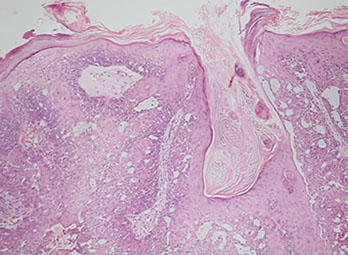

Pilomatrixoma

- aka calcifying epithelioma of Malherbe

solitary, bluish, firm (often calcifies), benign subepidermal spherical nodule

b9 hair follicle tumor

MC on face of kids or young adults

- 75% of childhood adnexal tumors

- can have multiple lesions in myotonic dystrophy

Sharply circumscribed cyst-like structure in dermis, possibly contiguous with hair follicle (may arise from hair matrix)

- can have inc mits (the malignant form is rare and usually very atypical)

- may have trichohyaline granules (which are usually seen in hair shafts)

3 cell types in fragmented cyst wall:

1) outer layer of blue (basophilic) basaloid martical cells with round nuclei and scant cytoplasm which dies and become dead keratin, which are the ghost cells

- imitate the cells in the root, or bulb of a normal hair follicle

2) mixed zone of eosinophilic cells c large round vesiculated nuclei

3) central zone sheets of keratinized pink "ghost" or "shadow" cells c distinct cell borders and central unstained nuclei

- difference from BCC: basaloid cells undergo abrupt keratinization and form "ghost" cells

Has foci of foreign body reaction, calcifications and ossification in shadow cell lobules

See melanin in shadow cells

Fibrotic stroma infiltrated with granulomatous inflam

Solid nests of basaloid cells may cause misdiagnosis of BCC

Ddx: Basal cell carcinoma c matrical differentiation (differs by continuity with epidermis and abrupt transition into shadow cells without the eosinophilic zone)